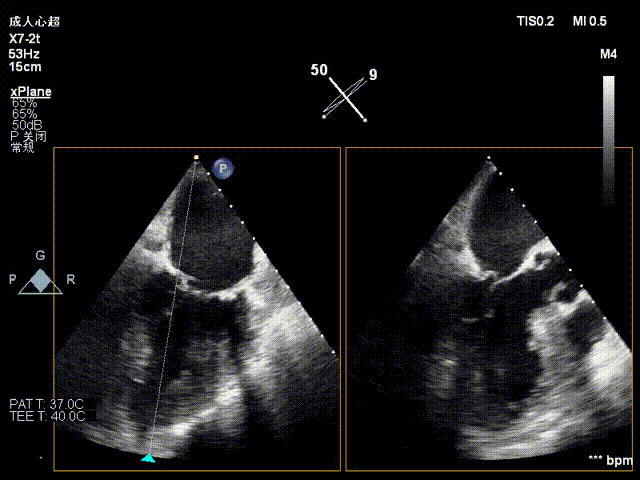

术前影像

手术难点/病例特征

该病例为二尖瓣重度反流,前叶A3区瓣叶脱垂并并腱索断裂,后叶瓣叶合并钙化,捕获瓣叶有一定难度。拟植入一枚NeoNova®C6(宽6mm)夹合器于3区脱垂处解决主要脱垂,然后根据残余反流和瓣口面积条件判断是否需要植入第二枚夹合器。